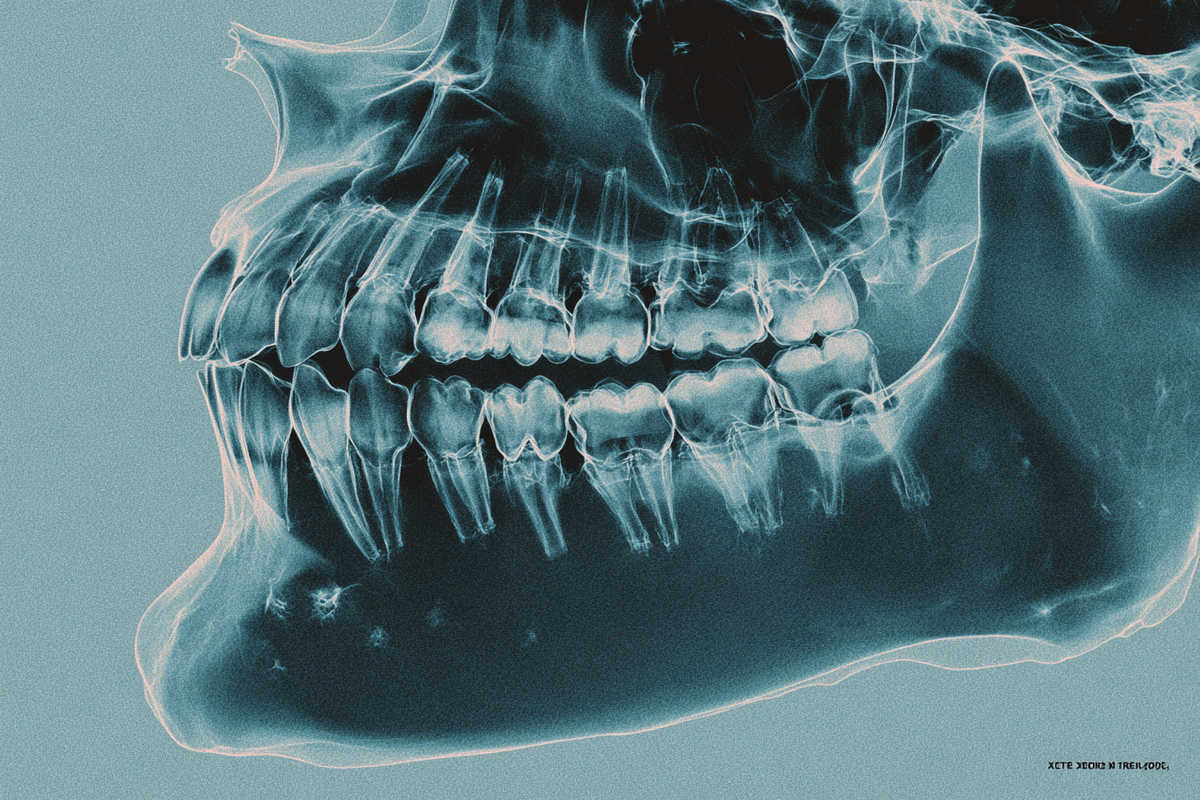

- Radiografía panorámica y TAC 3D para analizar volumen y densidad ósea.